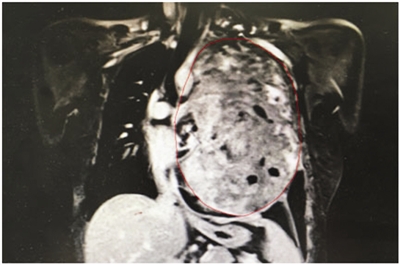

肿瘤CT影像

从CT片上一眼看去,左侧胸腔除了巨大的肿瘤几乎看不见任何正常器官和组织!肺被挤到了边缘,心脏、大血管、食管、气管等被完全挤向了右侧。与此同时,患者递来了其他医院的病理报告提示:梭形细胞肿瘤,考虑肉瘤。这是种对放化疗几乎无效的肿瘤,手术是最好、似乎也是唯一的选择。

术中还经历了几次过山车般的血液循环不稳定,在严密监测和药物治疗下患者生命体征维持平稳,肿瘤完全切除了下来,完整切除的肿瘤大小26cm×18cm×9cm,该肿瘤最长直径超过标准成人男子篮球直径(24.6cm左右)的长度。由于肿瘤的压迫几乎处于无功能状态的左侧肺组织慢慢膨胀起来,顺利地通气并发挥功能作用。手术成功了,这位年轻的母亲也渡过术后最危险的1周,现处于术后康复阶段。